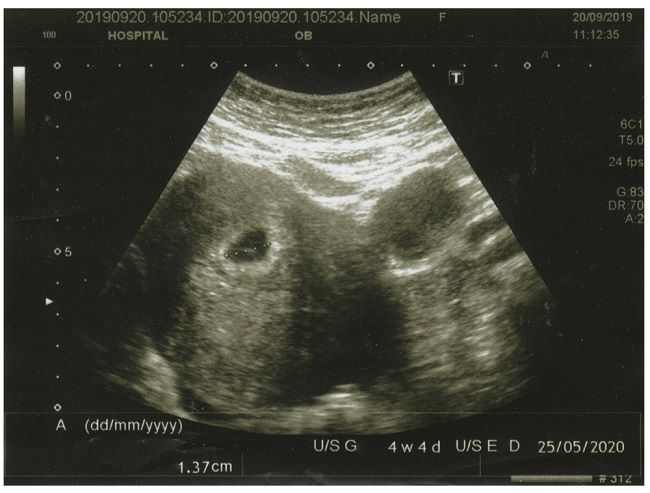

Tubuh Si Kecil juga mulai tampak lebih berisi, meski lapisan lemak di bawah kulitnya belum terlalu tebal. Berat badan Si Kecil yang makin bertambah menandakan organ-organ utamanya juga berkembang dengan baik. Biasanya, dokter akan mengukur pertumbuhan janin melalui pemeriksaan USG atau mengukur tinggi fundus perut Bumil.